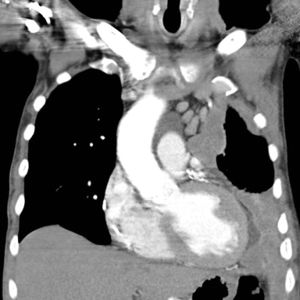

والأسبستوس مرض رئوي مزمن يصيب الرئتين نتيجة استنشاق ألياف الأسبستوس التي تتميز بدقتها الشديدة، والتي تعمل على خفض كفاءة الرئتين والجهاز التنفسي بشكل عام حيث يحدث اتصال مباشر بين الألياف والخلايا في الرئة ما يؤدي إلى تحول خبيث لهذه الخلايا، وبالتالي ينتج عن ذلك سرطان الرئة، ولوحظ أن المدخنين أكثر عرضة للإصابة بهذا المرض الذي تمكن خطورته في أن أعراضه تظهر بعد مرور 15 إلى 20 سنة.